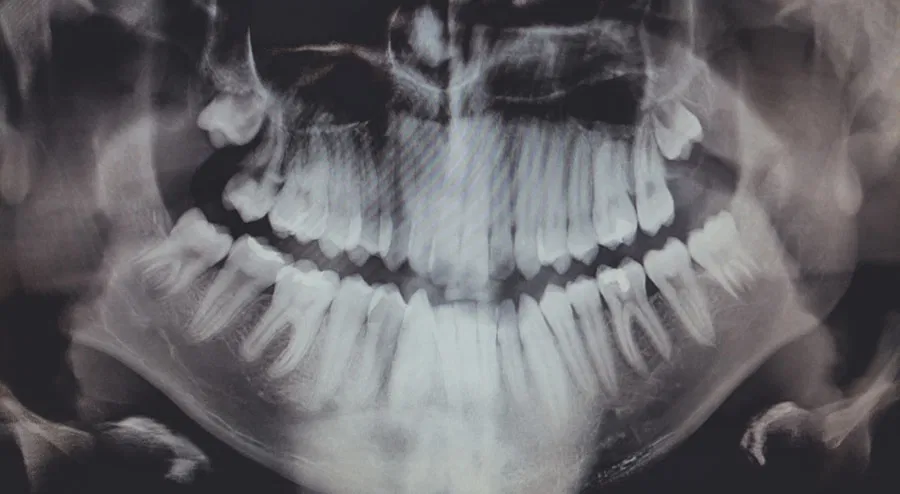

The process of wisdom teeth removal typically begins with a thorough examination by a dentist or oral surgeon. This examination often includes X-rays to assess the position of the wisdom teeth and determine whether they are impacted or at risk of causing problems. Based on this assessment, the dental professional will discuss the best course of action with the patient, which may include extraction if the teeth are deemed problematic.